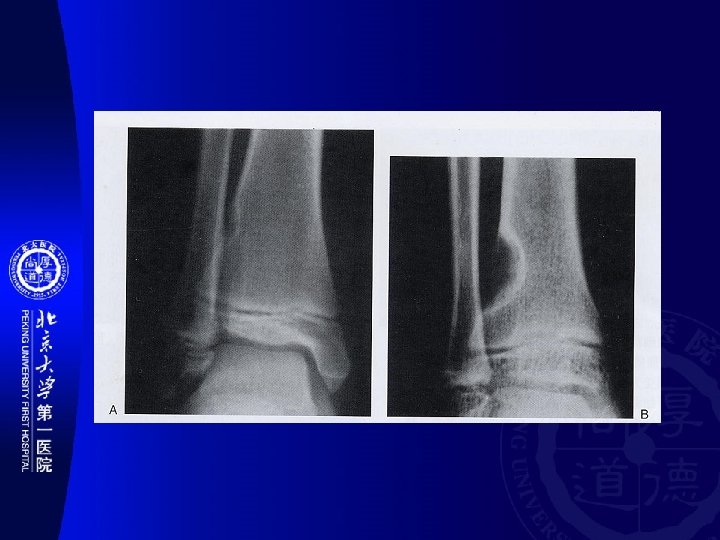

骨干 Diaphysis 干骺端 Metaphysis 骨骺 Epiphysis Other Myeloid 多发性骨髓瘤(Multiple myeloma) Epithelial 釉质细胞瘤(Adamantinoma) PNET 尤文氏瘤 (Ewing’s sarcoma) Osteoblast 骨样骨瘤 成骨细胞瘤(Osteoblastoma) 骨瘤 (Osteoma) 骨肉瘤(Osteosarcoma) Chondroblast 软骨瘤 软骨肉瘤(Chondrosarcoma) 骨软 骨瘤 软骨粘液样纤维瘤 Fibrous 非骨化性纤维瘤(nonossifying fibroma) 纤 维肉瘤(Fibrosarcoma) Chondroblast 成软骨细胞瘤(Chondroblastoma) Myeloid 骨巨细胞瘤(Giant cell tumor of bone) Notochord 脊索瘤(Chordoma)

� 骨好� 部位(SITE OF LONG BONE INVOLVEMENT ) (most primary bone tumors have favored sites within long bones; this may provide a clue to diagnosis). Diaphyseal intramedullary lesions: Diaphyseal lesions centered in the cortex: 釉� 瘤, 骨� 骨瘤 尤文氏瘤,淋巴瘤, 骨髓瘤,� �� 构不良,内生� 骨瘤 Metaphyseal intramedullary lesions: 骨肉瘤、� 骨肉瘤、 �� 肉瘤、�� 性骨囊� 、 � 脉瘤� 骨囊� Metaphyseal lesions centered in the cortex: 非骨化性�� 瘤(NOF) Epiphyseal lesions: � 骨母� 胞瘤 (Ch) and 骨巨 � 胞瘤(GCT) Metaphyseal exostosis: 骨� 骨瘤